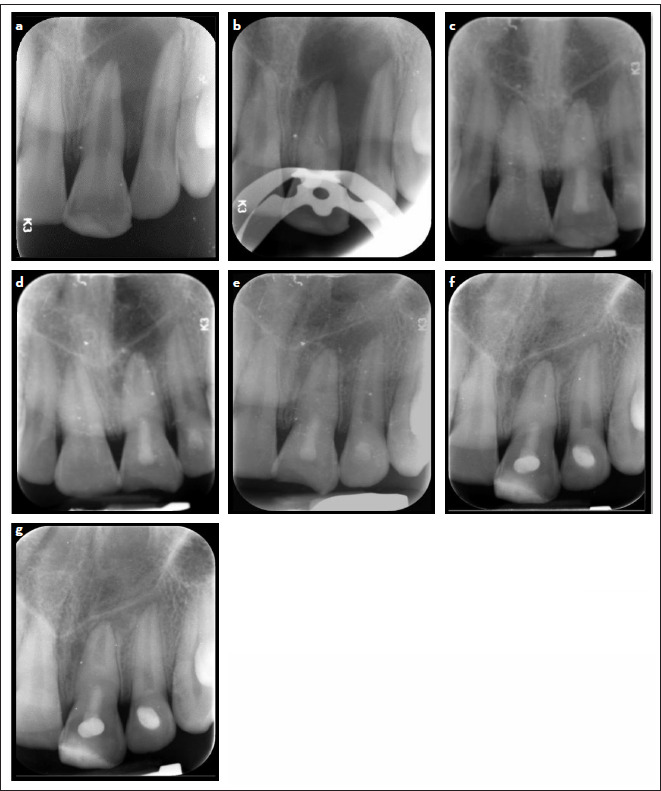

研究目的本随机对照研究旨在评估 Biodentine 与 MTA 相比,在牙髓坏死和根尖牙周炎的成熟单冠恒牙再生治疗后,Biodentine 作为牙髓间隙屏障在愈合根尖周病变和恢复牙髓敏感性方面的有效性:研究涉及 36 名患有牙髓坏死和根尖牙周炎的成熟牙齿患者。患者接受了利用血凝块技术的再生治疗。牙齿被随机分配到干预组(Biodentine)(18 个)或对照组(MTA)(18 个)。在长达 18 个月的随访中,对根尖周病变的愈合情况和牙齿的敏感性进行评估:研究分析了 31 名患者,其中生物素组和 MTA 组分别有两名和三名患者失去了随访机会。18 个月后,两组患者的根周病变均有效愈合;31 例患者中有 21 例(67.7%)愈合,10 例(32.3%)愈合,无失败病例。两组之间无明显差异(P=1.00)。超过 70% 的患者(31 位患者中的 22 位)恢复了牙齿的敏感性,各组间无统计学差异(P=0.703):结论:使用 MTA 或 Biodentine 血凝块进行再生治疗可有效解决根尖周病变,并恢复成熟牙齿的敏感性。

Methods: The study involved 36 patients with mature teeth with necrotic pulp and apical periodontitis. The patient underwent a regenerative treatment that utilized the blood clot technique. Teeth were randomly allocated to either the intervention, Biodentine, group (n=18) or the control, MTA, group (n=18). The healing of periapical lesions and tooth sensibility were evaluated throughout follow-up visits for up to 18 months.

Results: The study analyzed 31 patients; two patients within the biodentine group and three in the MTA group were lost to follow-up. After 18 months, both groups showed effective healing of periradicular lesions; 21 out of 31 patients (67.7%) were healed, ten patients (32.3%) were healing, and no failure cases occurred. There were no significant differences between the groups (p=1.00). More than 70% (22 out of 31 patients) regained their sensibility in their teeth, and the groups had no statistically significant difference (p=0.703).

Conclusion: Regenerative treatment using blood clots with either MTA or Biodentine effectively resolved periapical lesions and regained the sensibility of mature teeth.